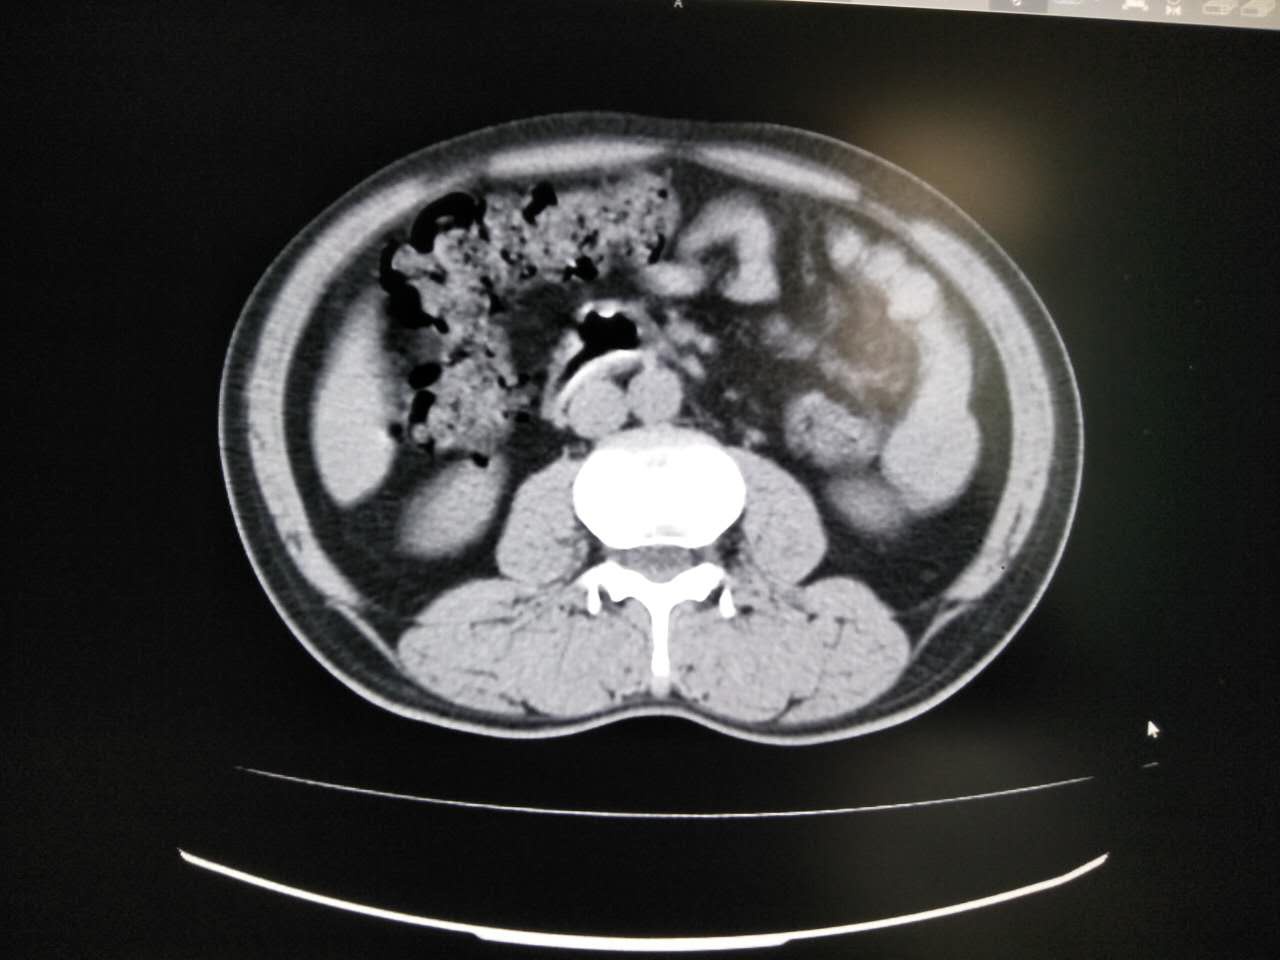

胃肠道CT 检查如要获得高质量的图像,肠道准备非常重要。如果小肠内有食物残渣, 就会影响肠腔的充盈与扩张,对于胃肠壁上较浅的病变难以显示。以下两例就是胃肠道未作准备,内容物较多,影响对比度,从而影响检查效果。

以下几例是胃肠道对比度较好的例子,可以清晰显示胃肠壁有无病变。